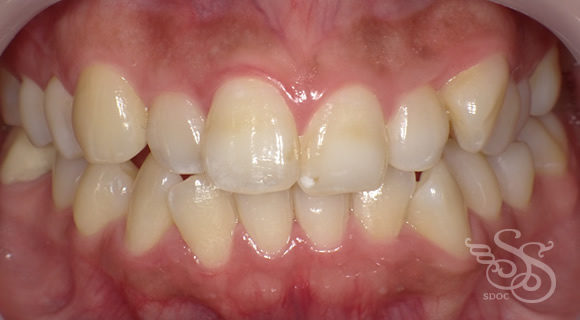

久しぶりに会った友人に「整形した?」と言われた患者さま

術前

術後